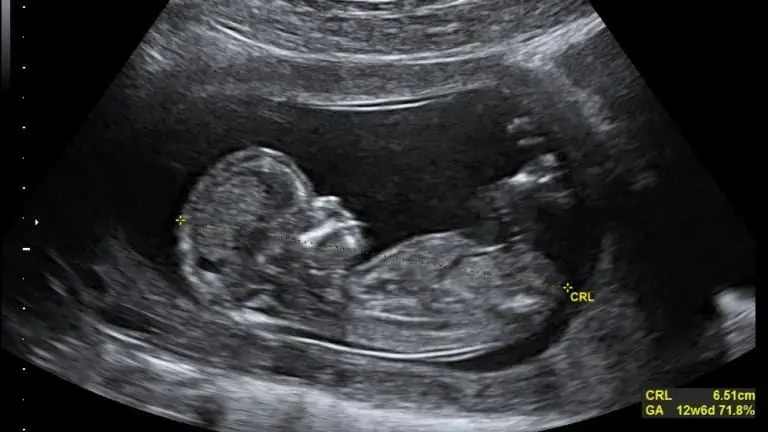

Общая проблема прав на аборт сводится к двум вещам: перспективе и праву. Большинство из тех, кто считает аборт прогрессивным с точки зрения прав женщин, не верят, что жизнь начинается с зачатия. Для них права человека начинаются с момента рождения, хотя даже тогда границы размыты, особенно если учесть, что в некоторых местах в мире разрешено прерывание беременности во время родов. Если плод для них всего лишь скопление клеток или даже силуэт ребенка, привязанного к плаценте в матке матери, то он и близко не сравним с рожденным ребенком или даже с ребенком-мигрантом, разлученным со своими родителями на границе.. Обе ситуации абсолютно ужасны, и я никоим образом не оправдываю разлуку детей с их близкими. Я могу понять, как такой взгляд может отвергнуть идею о том, что «потенциальный» ребенок такой же человек, как и «рожденный» ребенок. Но если жизнь действительно начинается с зачатия и в матке действительно находится реальный физический человек, эти два сценария можно сравнить. Но очевидная разница заключается в том, что у ребенка-мигранта, скорее всего, будет шанс воссоединиться со своими родителями, в то время как у нерожденного ребенка (после ужасного расчленения) может никогда не быть возможности встретиться с их родителями.